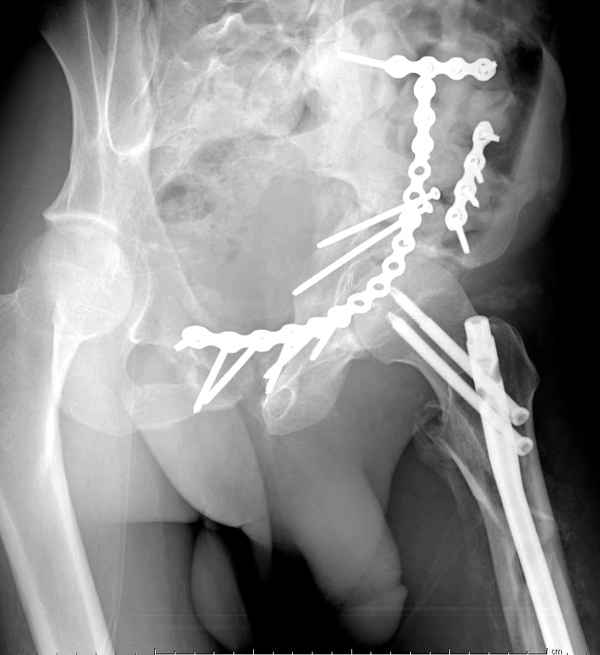

Из того минимума, что представлено, мне кажется, мы имеем дело с двухколонным переломом вертлужной впадины. Обычно медиальный (центральный) "вывих" головки встречаются в сложных двухколонных переломах со смещением.

По-моему, надо готовить больного к будущей артропластике, но без опоры на задний столб невозможно удержать протез. Опорная конструкция (кольца и т.д.) должны иметь опору, и поэтому мы бы сделали реостеосинтез задним доступом. При надобности остеотомия и рутинная фиксация с межколонными винтами.

Здесь несколько вариантов двухколонных свежих переломов, которые были оперированы из одного-заднего, а также из двух: переднего и заднего доступов.